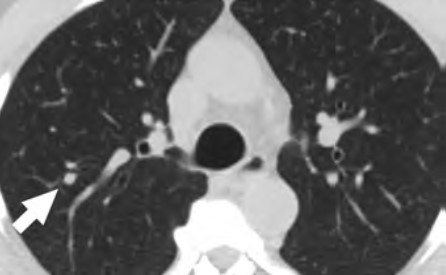

At the individual level, some of the barriers include decreased opportunities to provide accurate smoking history in the EMR, cost concerns related to insurance coverage of LCS and subsequent followups (Fig. 3), challenges to understanding LCS results when examinations show abnormal findings, fragmentation of care for management of abnormal LCS results and incidental findings, and difficulties navigating the complexities of health care systems [4, 8, 10]. Cost transparency and cost concerns are areas of active research, because cost influences how patients access and use health services [2]. For example, a recently published study evaluated the out-of-pocket cost of invasive procedures after LCS and showed that the rates of invasive procedures in commercially insured populations exceed those of invasive procedures in clinical trial participants [2].

At the individual level, facilitators of opportunities for LCS include increasing the opportunities to provide an accurate smoking history through educational campaigns and additional opportunities in other health encounters to capture LCS eligibility information [24]. For identifying LCS-eligible patients, leveraging teachable moment and care coordination strategies during existing routine appointments can be effective. A previous study showed that among women undergoing screening mammography who were given a brief survey to assess LCS eligibility, only a small fraction of LCS-eligible women had undergone LCS [25].

Facilitating care coordination and overcoming transportation barriers can provide additional opportunities for patients to undergo LCS [4, 26]. For example, same-day screening appointments at the time of other medical appointments have been shown to be beneficial to patients who have trouble with transportation, taking time off from work, and finding assistance with dependent care, and this strategy could be expanded to be offered to patients eligible for LCS [27]. Concerns about the costs of LCS can be alleviated by providing information about expected costs related to LCS and by offering information about diverse financial support options provided by institutions. People who are uninsured or have concerns about out-of-pocket expenses related to LCS can be referred to community health care workers and patient navigators who can assist patients in identifying grant funding and institutional financial assistance programs to cover LCS among patients who do not have insurance or have a low income [22, 28]. Health care workers can also assist patients in navigating the complexities of the health care system and clarify additional questions related to their LCS results [22].